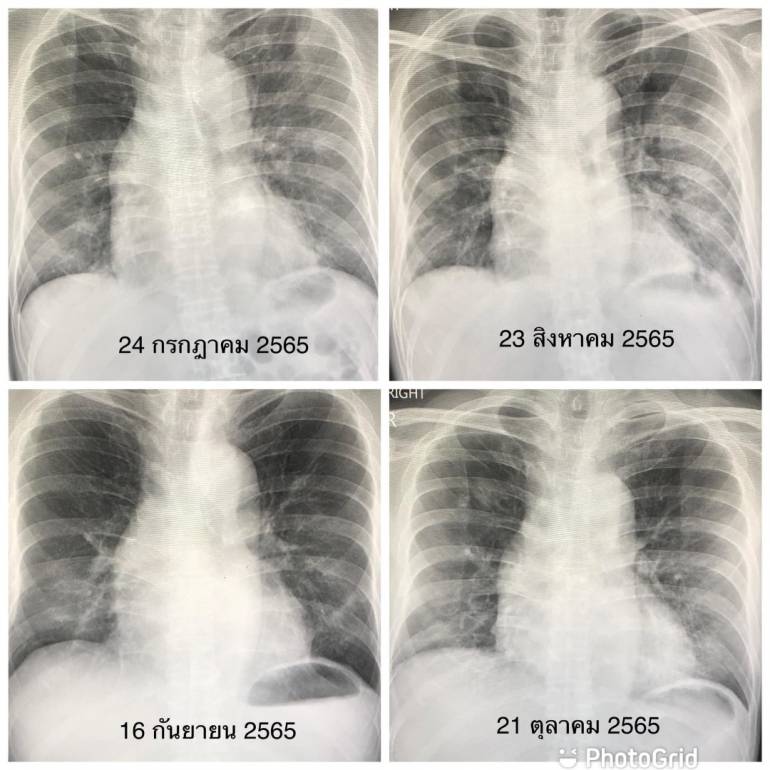

ภาพถ่ายเอกซเรย์

Posts: ภาพถ่ายเอกซเรย์